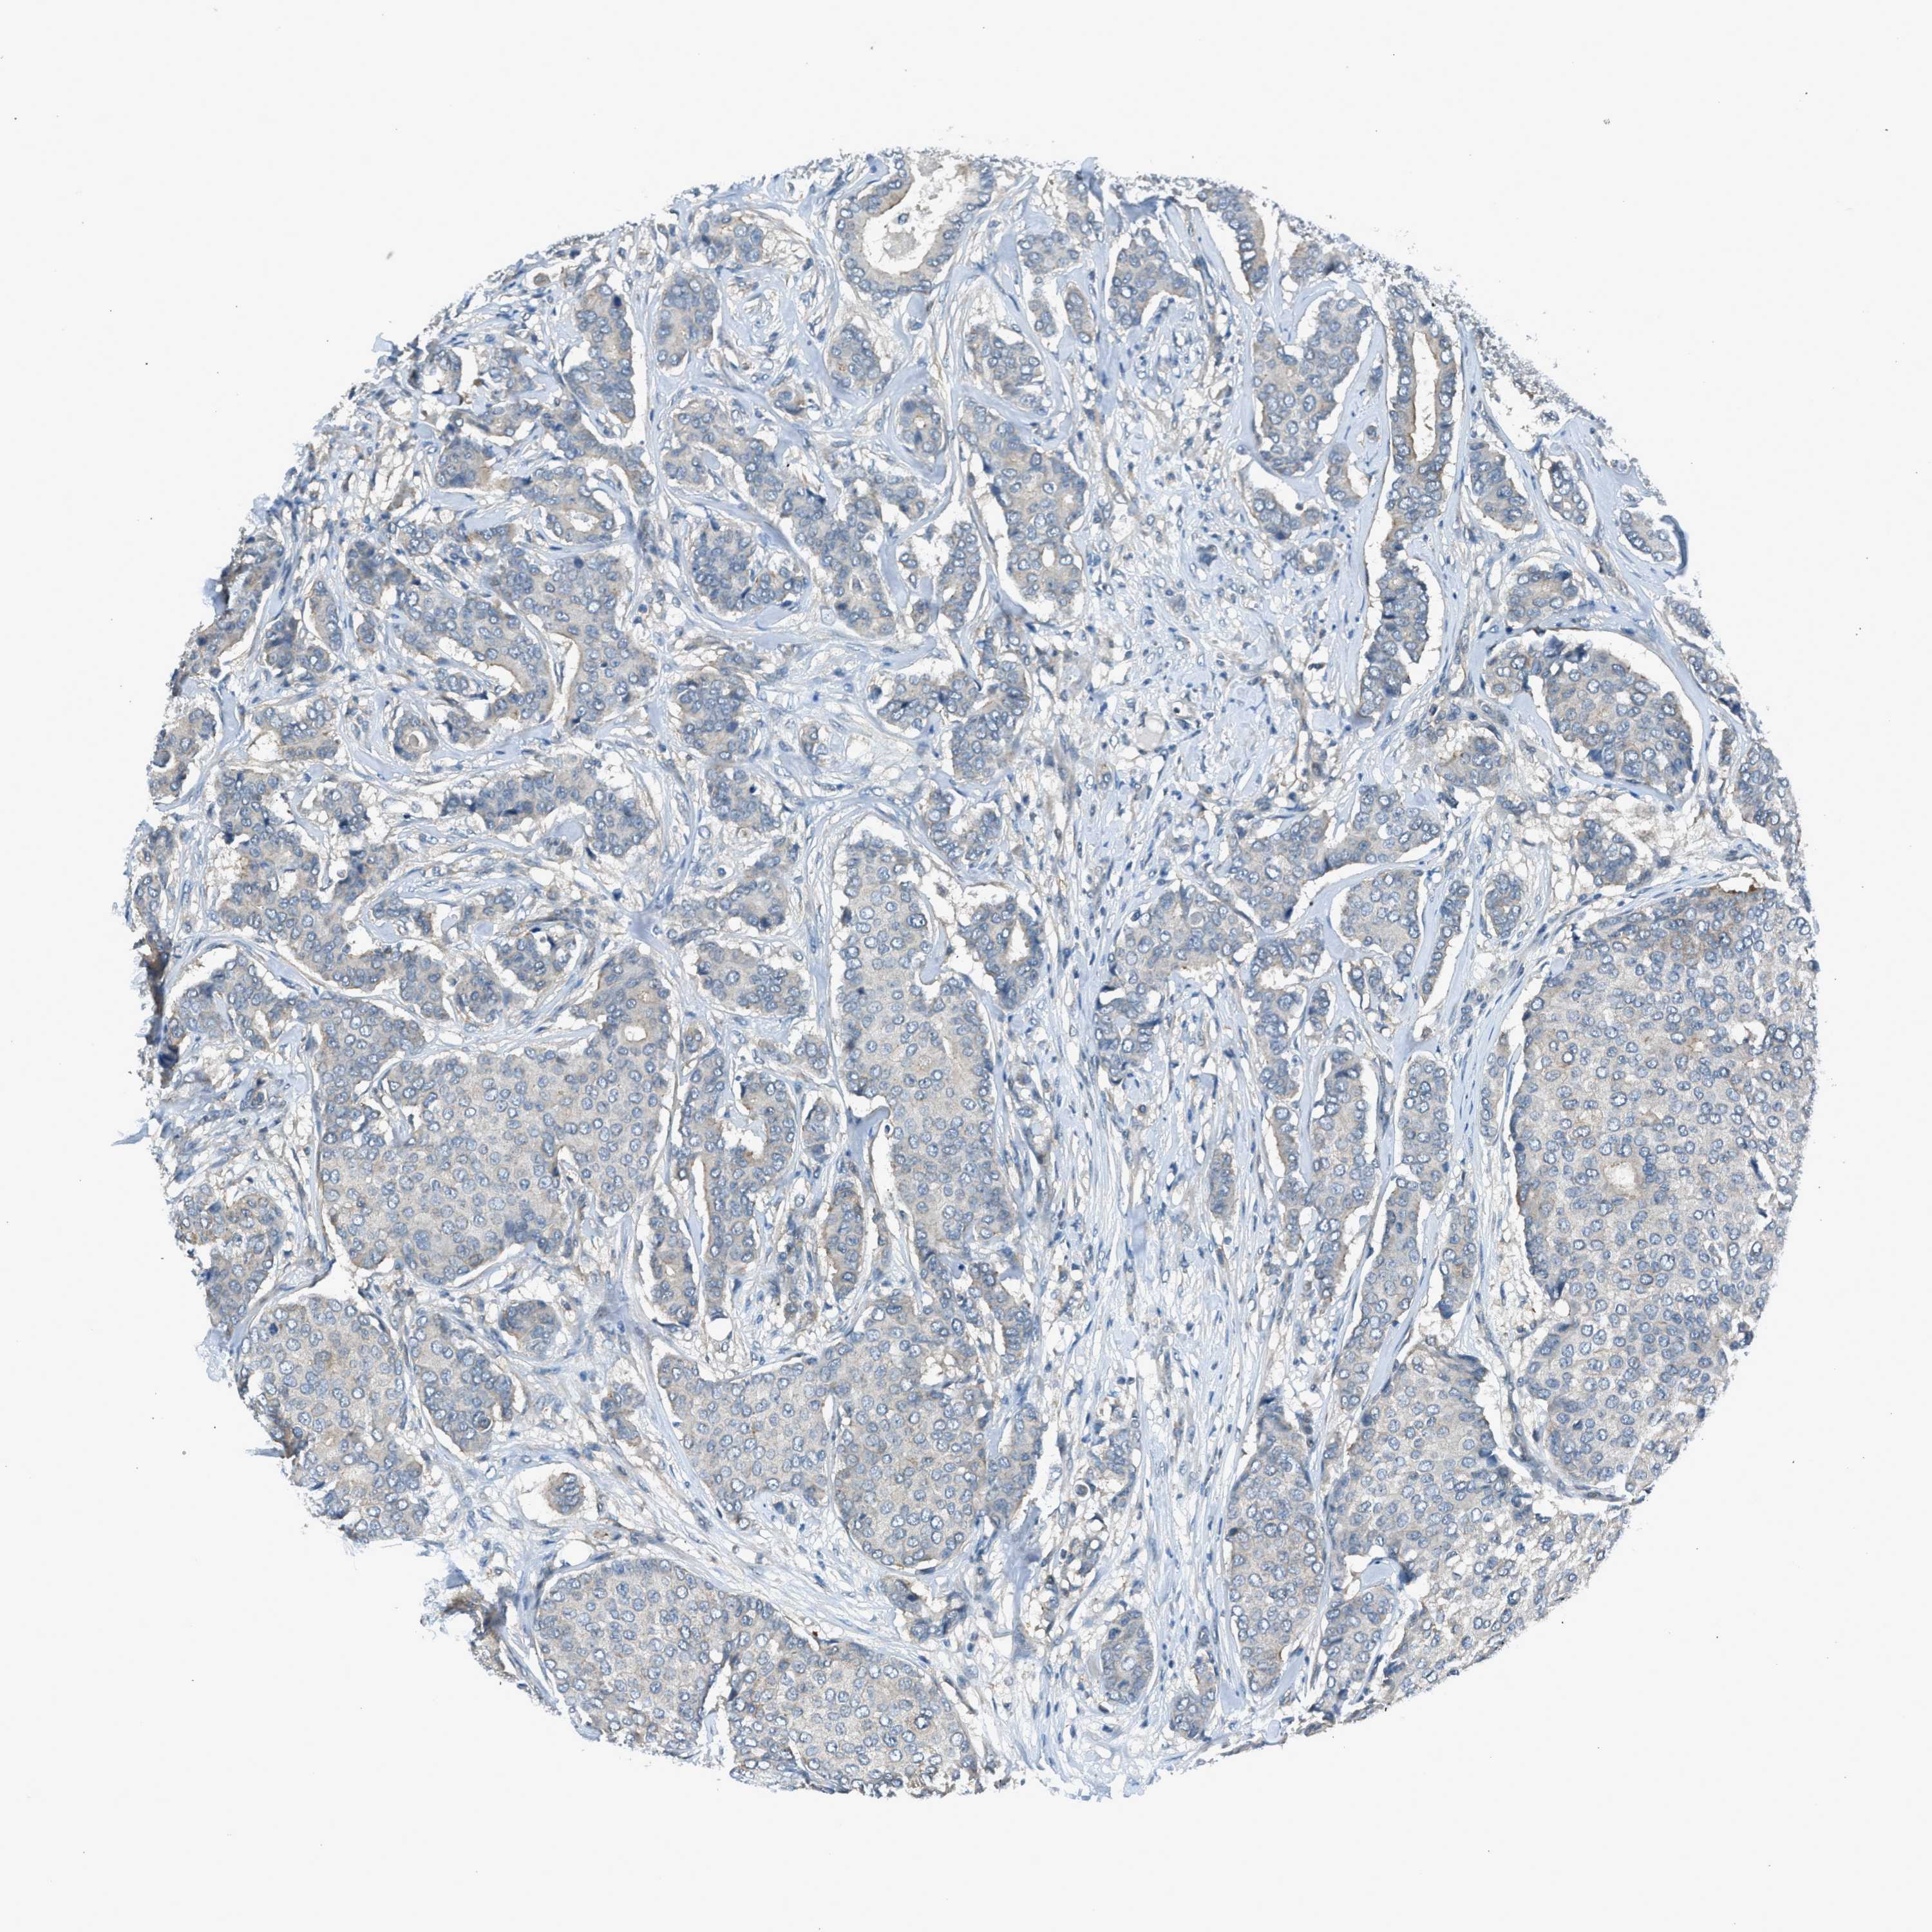

CANCER BREAST CANCER Show tissue menu

BRCA TCGA BRCA VALIDATION PROTEIN EXPRESSION